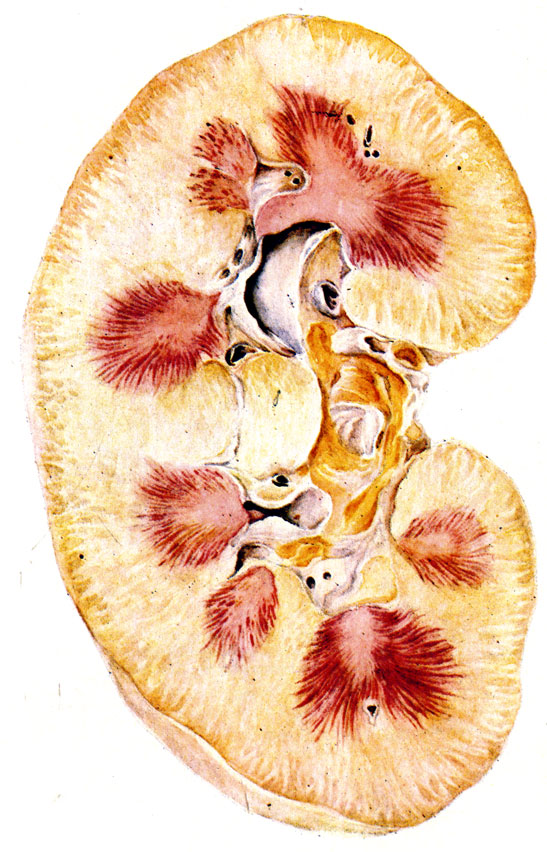

Механизм остро го диффузного гломерулонефрита